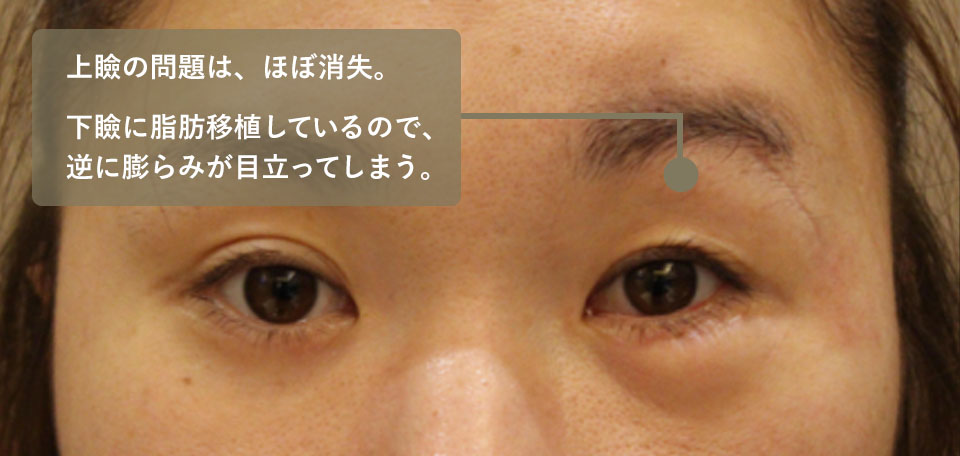

B大学病院で2回手術をされていますが、左眼の重度の眼球陥凹が残存しており、左右非対称の顔貌となってしまっています。また下眼瞼へなぜか脂肪移植されているためこれも左右差を助長する原因となっています。

CTでは再建手術を2回されているものの、骨壁を治すことが出来ていないため、眼窩の断面積が縮小していません。これが眼球陥凹の大きな原因でした。

手術は白目(結膜)の切開から行ったため、皮膚に傷は残っていません。人工骨で足場を作り、その上にプレートが乗せました。

術後のCTを見ると眼窩の断面積が正常である右に近づいているのが分かります。